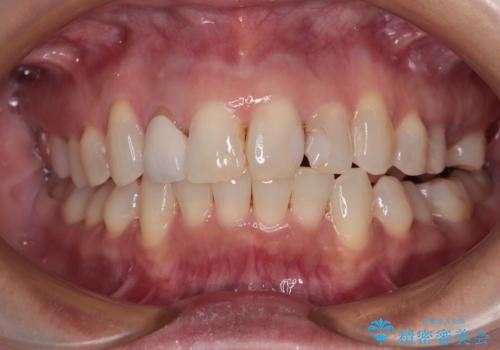

前歯のデコボコとむし歯治療の跡 インビザライン矯正とオールセラミッククラウン治療

- 前歯のセラミッククラウンの縁が見えることが気になってから、デコボコも気になるようになってきたとのことで来院された患者様です。

デコボコの程度は中等度であったため、インビザライン・モデレートパッケージにて歯列を整えることとしました。

セラミッククラウンの装着されていた前歯と、大きな修復治療の跡がある反対側の歯は、矯正治療後に補綴治療を行うこととしました。